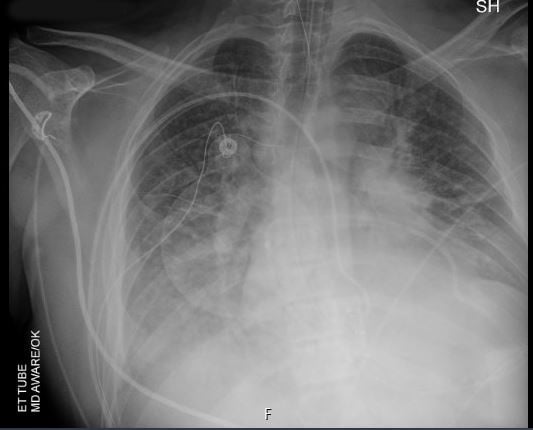

A 30-year-old man presents with dyspnea and is found to have an anterior mediastinal mass, as well as supraclavicular lymphadenopathy; biopsy of the mass is consistent with thymic carcinoma. Imaging shows his anterior mediastinal mass, lung and diaphragmatic lesions consistent with metastatic malignancy, and probable pericardial involvement with small pericardial effusion (Figures 1, 2, 3, and 4).

Two months later, he presents to the emergency department with worsening shortness of breath, fatigue, and hoarseness. Bedside echocardiography shows enlarged pericardial effusion, with thickness of 2.65 cm; dilated inferior vena cava without respiratory variation; and partial diastolic collapse of the right atrium and right ventricle. A pericardial drain is placed, and 750 mL of serous fluid is removed from the pericardial space. Approximately 30 minutes after the procedure, the patient becomes increasingly dyspneic and hypoxic, with SpO₂ 83% despite heated high-flow blender oxygen at 100% and 60 L/minute. Venous blood gas analysis shows pH 7.02 and PCO₂ 87 mm Hg. Emergent endotracheal intubation is performed, with exuberant pink frothy secretions seen emanating from the trachea during laryngoscopy. Chest radiographs from before his pericardiocentesis and after his intubation are shown in Figures 5 and 6.

Fig. 5: Chest radiograph prior to pericardiocentesis. -